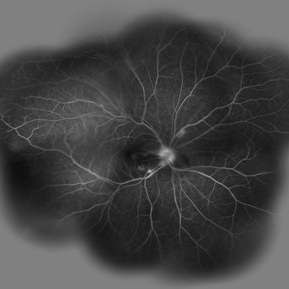

Behcet's Disease Behcet's DiseaseMar 13 2013 by Hamid Ahmadieh, MD Mid phase FA of the left eye of a 23-year-old man with retinal vasculitis due to Behcet's disease . Photographer: Solmaz Shahmohammad , Negah Eye Center, Tehran Imaging device: Heidelberg Spectralis Condition/keywords: retinal vasculitis

Behcet's Disease Behcet's DiseaseMar 13 2013 by Hamid Ahmadieh, MD Late phase FA of the left eye of a 23-year-old man with retinal vasculitis due to Behcet's disease . Photographer: Solmaz Shahmohammad, Negah Eye Center, Tehran Imaging device: Heidelberg Spectralis Condition/keywords: retinal vasculitis